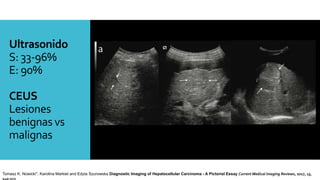

Ultrasonido

S: 33-96%

E: 90%

CEUS

Lesiones

benignas vs

malignas